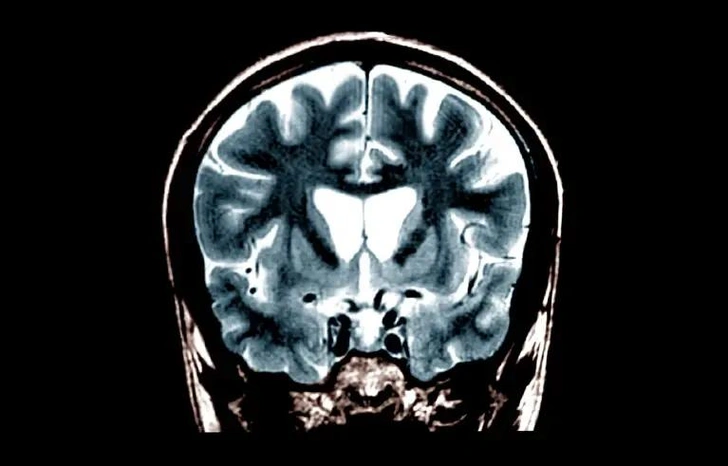

Для проведения лечения требуется длительная операция, во время которой врачи с помощью магнитно-резонансной томографии точно вводят канюлю через небольшие отверстия в черепе. Затем препарат медленно вводится в полосатое тело — часть мозга, которая первой и сильнее всего страдает от болезни Хантингтона.